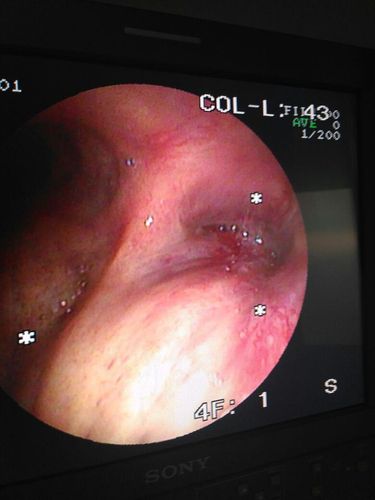

"Tadi saya melakukan teropong saluran napas. Ini gambaran kanker paru di saluran napas utama kanan. Menutup total saluran napasnya," kata dr Frans kepada detikHealth dan ditulis Selasa (31/10/2017).

Menurut dr Frans kanker yang dialami oleh sang pasien sudah cukup lanjut sehingga prognosisnya untuk bisa bertahan hidup kecil. Sang pasien adalah seorang petani kebun karet dan memang punya riwayat kebiasaan merokok sehari sampai dua bungkus.

"Penelitian medis sudah banyak memberi bukti korelasi signifikan (rokok dan kanker -red). Dia petani kebun karet tak terpajan bahan kimia inhalan atau hirupan lain," kata dr Frans.